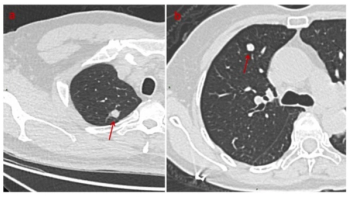

Offering comparable sensitivity to radiologists for detecting contralateral breast cancer on mammography images, an emerging adjunctive AI software may also facilitate earlier diagnosis, according to study findings presented at the at the 2024 American Society of Clinical Oncology (ASCO) Annual Meeting.